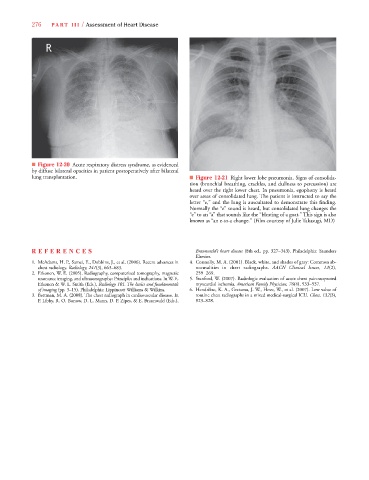

■ Figure 12-20 Acute respiratory distress syndrome, as evidenced

by diffuse bilateral opacities in patient postoperatively after bilateral

lung transplantation. ■ Figure 12-21 Right lower lobe pneumonia. Signs of consolida-

tion (bronchial breathing, crackles, and dullness to percussion) are

heard over the right lower chest. In pneumonia, egophony is heard

over areas of consolidated lung. The patient is instructed to say the

letter “e,” and the lung is auscultated to demonstrate this finding.

Normally the “e” sound is heard, but consolidated lung changes the

“e” to an “a” that sounds like the “bleating of a goat.” This sign is also

known as “an e-to-a change.” (Film courtesy of Julie Takasugi, MD)